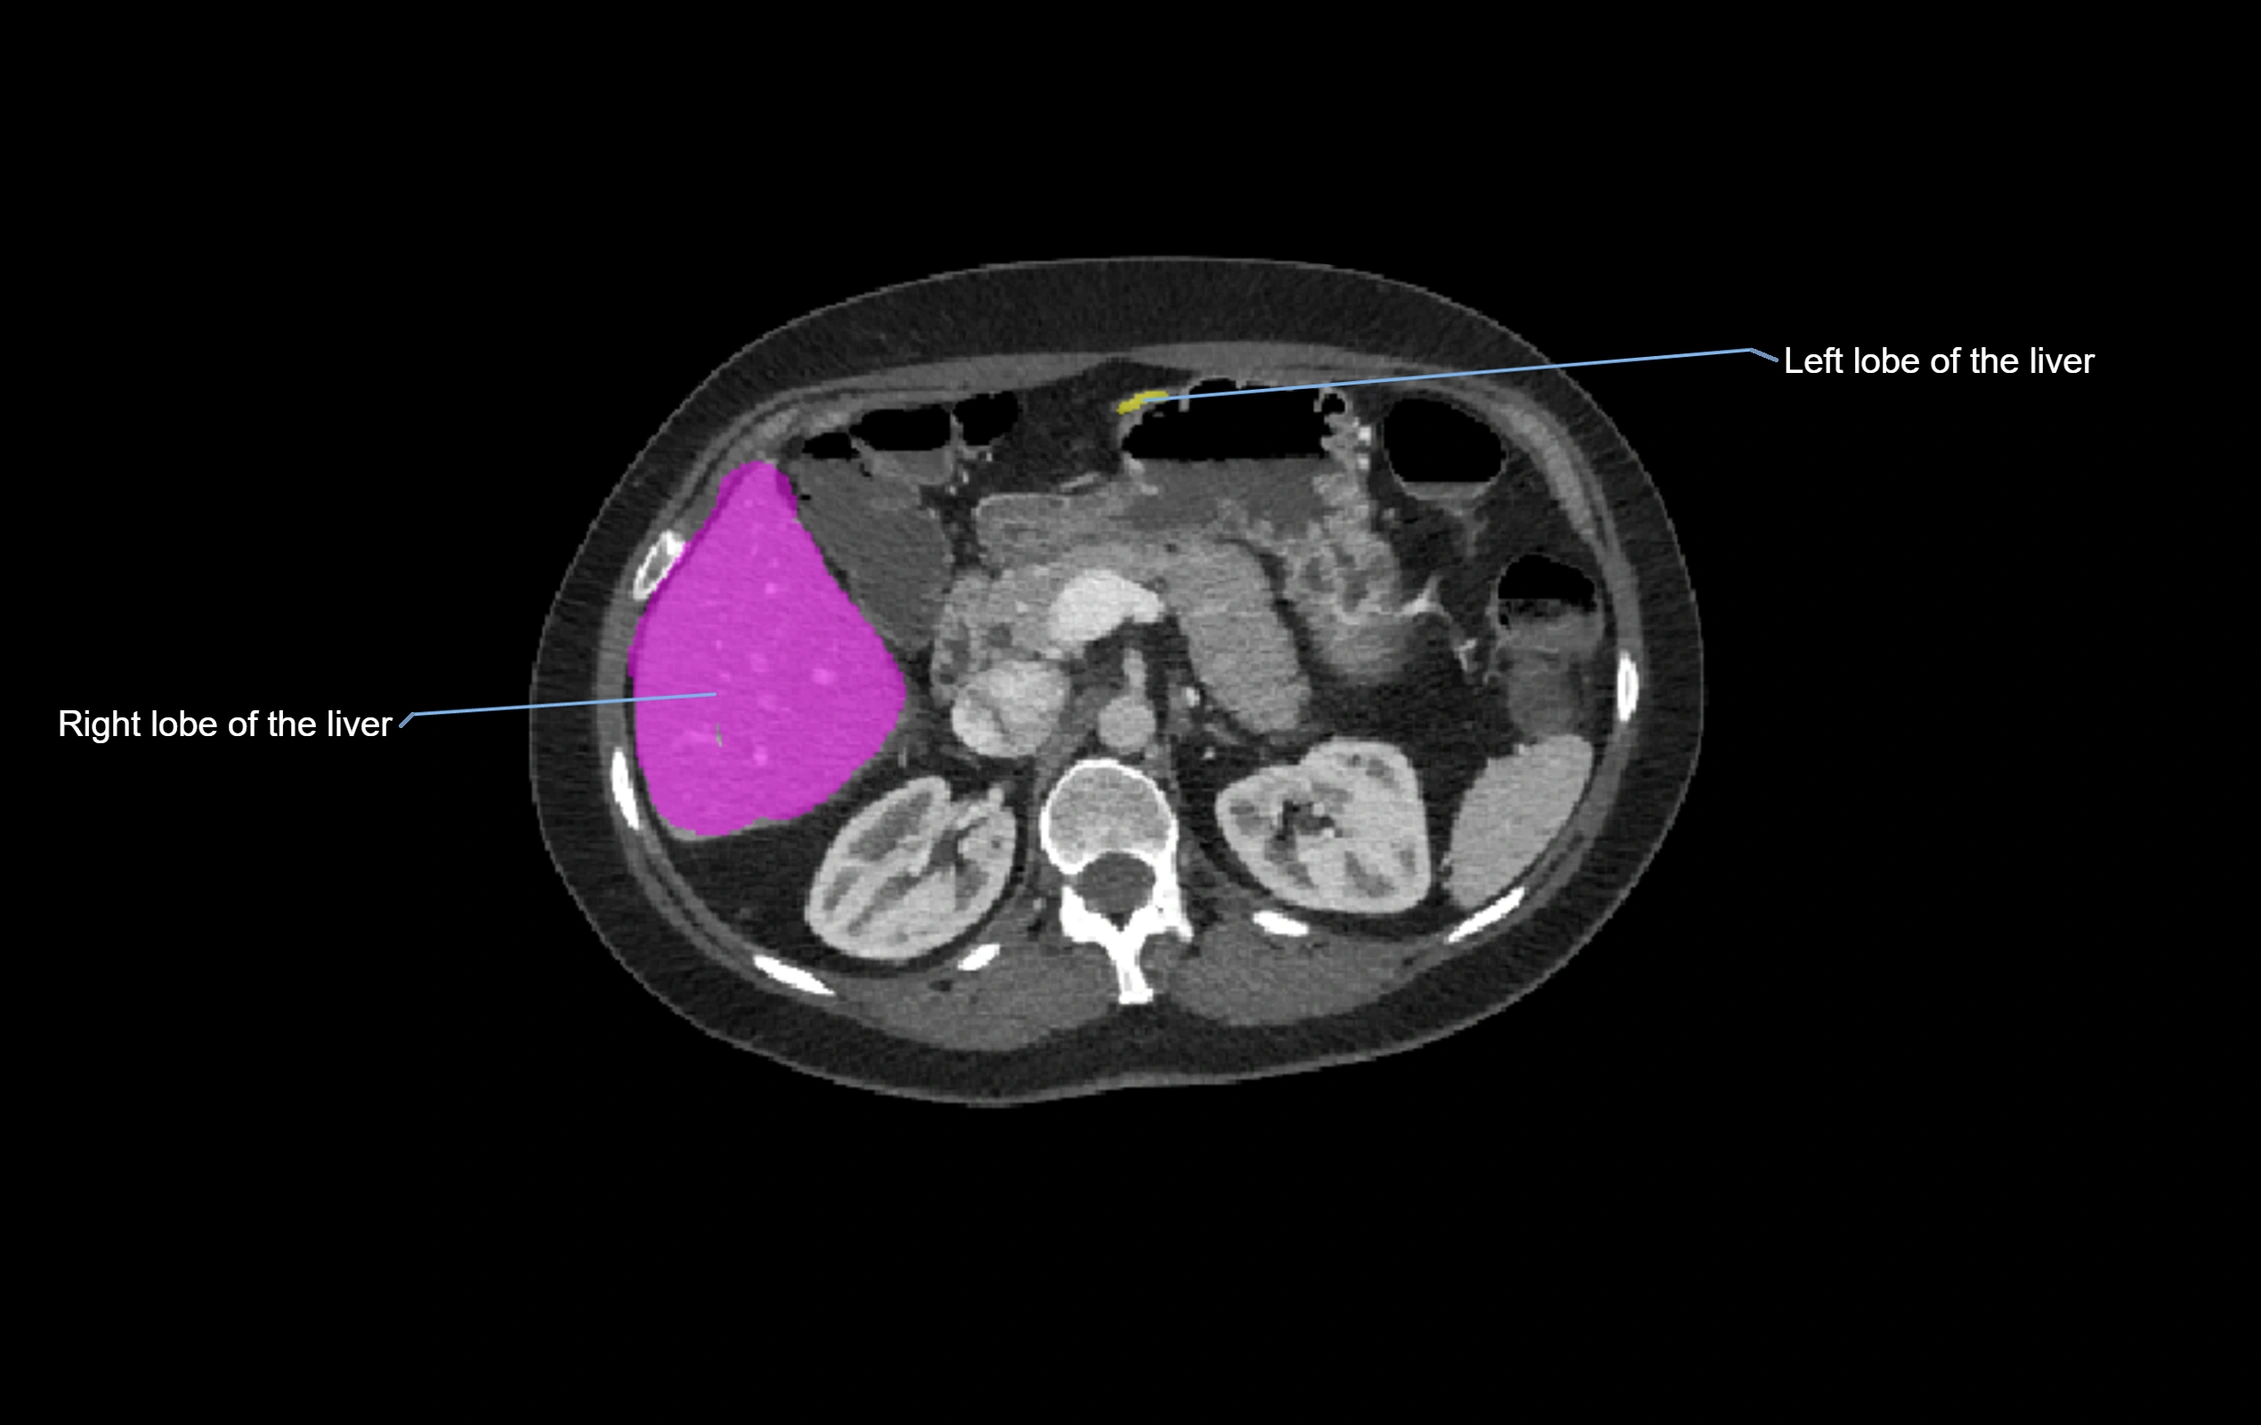

CT Image

image